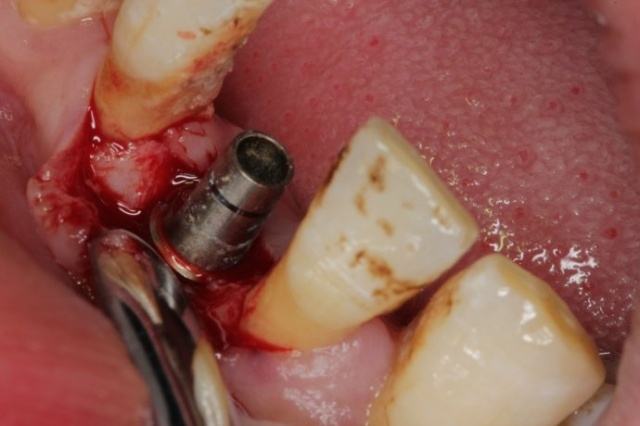

術(shù)中:

因?yàn)槭中g(shù)的時(shí)候因?yàn)榇蛄寺樗?,在手術(shù)后爸爸也說(shuō)沒(méi)有疼痛感,所以整個(gè)手術(shù)過(guò)程都比較輕松,也許是因?yàn)樽隽耸中g(shù),爸爸告訴醫(yī)生說(shuō)有些不適應(yīng),醫(yī)生說(shuō)是正常的情況,在麻藥勁之后還會(huì)有疼痛感,然后告訴我們需要注意的各種事項(xiàng),之后就回家了。

3-20022320243S06.jpg